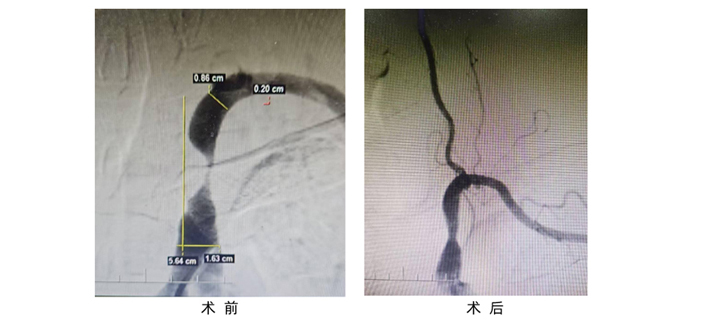

孫銀住院進(jìn)一步檢查,DSA血管造影檢查顯示:左側(cè)鎖骨下動(dòng)脈近端重度狹窄(重度,96%),與陶主任的判斷相一致。數(shù)字減影血管造影( DSA) 是目前該病診斷的金標(biāo)準(zhǔn),可以清楚地顯示病變位置、程度,有利于明確診斷及指導(dǎo)手術(shù)方式的制定。

經(jīng)陶主任團(tuán)隊(duì)綜合評(píng)估及與患者及家人充分溝通,12月24日局麻下行“鎖骨下動(dòng)脈支架置入術(shù)”,并邀請(qǐng)了業(yè)內(nèi)專家現(xiàn)場(chǎng)指導(dǎo)。術(shù)中患者神志清晰,順利置入支架,將閉塞的血管開(kāi)通,恢復(fù)血流。

術(shù)后,患者左側(cè)橈動(dòng)脈搏動(dòng)有力,左右上肢血壓分別是131/74 mmHg、141/85 mmHg,恢復(fù)對(duì)稱,頭暈和左上肢乏力癥狀得到了明顯緩解。12月27日,患者已順利出院。 陶國(guó)良表示:由于該患者長(zhǎng)期高血壓,吸煙病史,血管動(dòng)脈硬化導(dǎo)致手術(shù)操作困難。而“鎖骨下動(dòng)脈支架置入術(shù)”有三大難點(diǎn):首先,對(duì)病變部位定位精準(zhǔn)度要求高。鎖骨下動(dòng)脈近端的解剖位置特殊,周圍結(jié)構(gòu)復(fù)雜,要準(zhǔn)確找到狹窄部位并精準(zhǔn)放置支架有一定難度,需要憑借豐富經(jīng)驗(yàn)結(jié)合影像學(xué)精準(zhǔn)判斷。其次,血管迂曲情況處理難。部分患者鎖骨下動(dòng)脈可能存在迂曲,這會(huì)使導(dǎo)絲、導(dǎo)管通過(guò)困難,增加手術(shù)操作時(shí)長(zhǎng)以及相關(guān)并發(fā)癥出現(xiàn)的幾率。再者,支架選擇與釋放有難度。需要根據(jù)狹窄的具體長(zhǎng)度、直徑等情況選擇合適規(guī)格的支架很關(guān)鍵,并且在釋放支架時(shí),確保其位置準(zhǔn)確、貼壁良好。